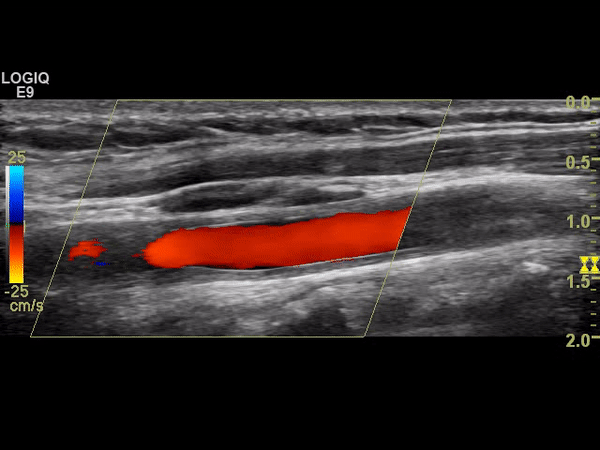

A 28 year old lady presented with transient left arm weakness. This had been preceded by a two month history of fever, malaise, generalized arthralgia and a more focal tenderness in her neck bilaterally. She described subtle weakness raising the possibility of a stroke.

Her investigations included a carotid Doppler (Figs 1, 2 shows grey scale and Doppler cineclips of the right common carotid artery/bulb).

Figure 2 |